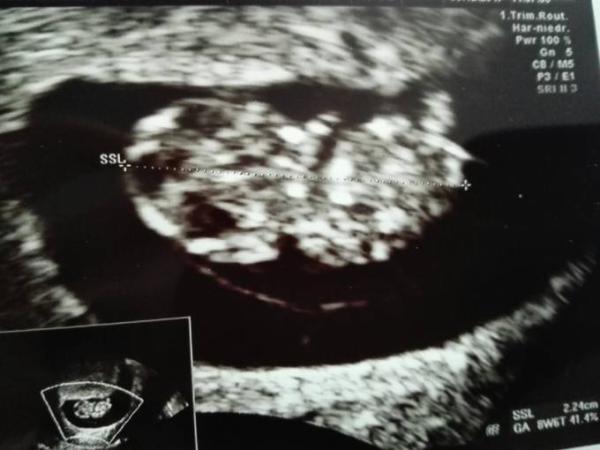

Dem Baby geht aber gut. Es ist jetzt 2,2 cm groß, was zu 8+6 passt, so, wie ich es mir ausgerechnet habe. Trotzdem steht als ET jetzt der 6.11. im Mutterpass und als Schwangerschaftswoche im Gravidogramm 8+2 und unter sonstiges,dass die SSL 8+6 entspräche.